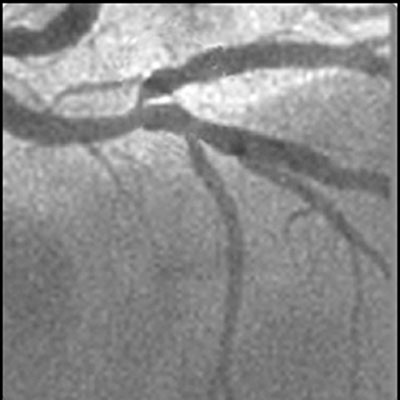

D’après l’étude ADAPT-DES, le guidage par échographie intravasculaire est associé à une modification de la stratégie d’ICP dans 74 % des cas.2 La plupart du temps, la taille du stent ou du ballonnet s’est trouvée plus importante et une post-dilatation s’en est suivie. Par ailleurs, l’étude a rapporté que de plus grandes surfaces de stent ont entraîné la réalisation d’une échographie intravasculaire à la fois pré-ICP et post-ICP alors que seule une échographie intravasculaire post-ICP était auparavant réalisée.

D’après l’étude ADAPT-DES, le guidage par échographie intravasculaire est associé à une diminution de la survenue d’évènements cardiaques indésirables majeurs (MACE) de 34 % à deux ans (4,9 % vs 7,4 %, p < 0.001).3

De nombreuses preuves provenant d’essais cliniques randomisés, d’études observationnelles et de rapports d’analyses comparatives démontrent que le guidage par échographie intravasculaire est associé à une diminution du nombre de MACE.4,5,6,7,8